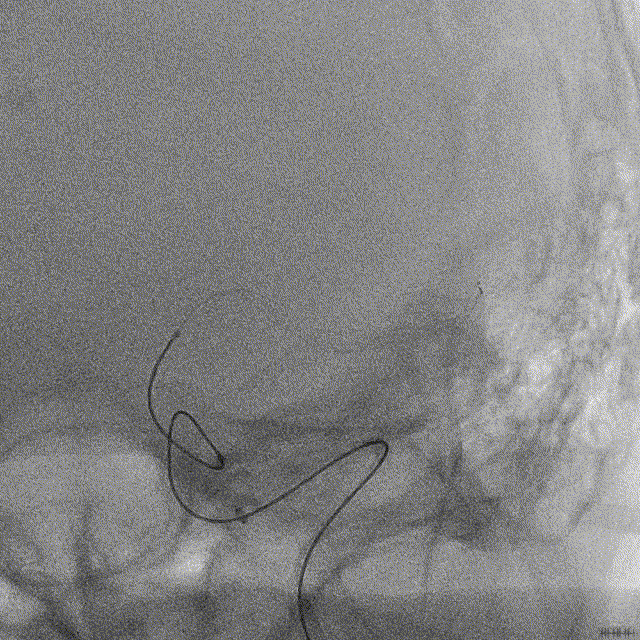

NeuroHawk Case 7